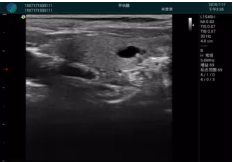

清晰顯示腺體內(nèi)低回聲快影,邊界清晰,包膜較光滑

確定進(jìn)針路徑并實(shí)時(shí)監(jiān)測(cè)抽吸針與腫塊位置關(guān)系

抽吸針進(jìn)入腫塊內(nèi)部進(jìn)行旋切

抽吸過(guò)程中可見(jiàn)腫塊明顯縮小,并根據(jù)腫塊位置改變針道位置

抽吸旋切后再進(jìn)行超聲復(fù)查,原腫塊區(qū)域未見(jiàn)殘留組織及出血